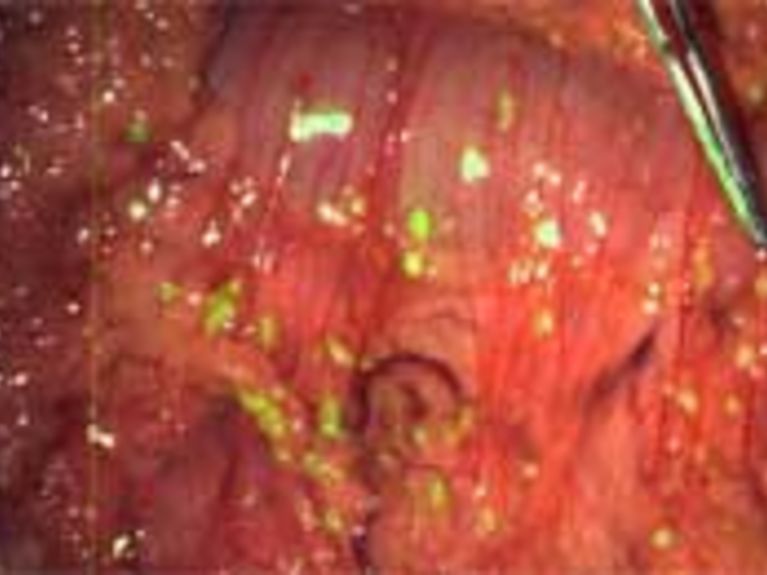

The new technology is based on a real-time camera that can detect fluorescence in tissue. This makes it possible to find tiny tumours inside the body without damaging the tissue that surrounds them. What makes the collaborative research so innovative is its clinical application. Before the technology was introduced it was very difficult, if not impossible, to diagnose small tumour foci during an operation. Now surgeons can assess findings while an operation is still in progress. “This precise and innovative method lays the groundwork for a paradigm shift in interventional procedures,” says Prof. Vasilis Ntziachristos. “Thanks to this application we can now accurately detect and identify disease to achieve more reliable results. It greatly reduces artefacts.”